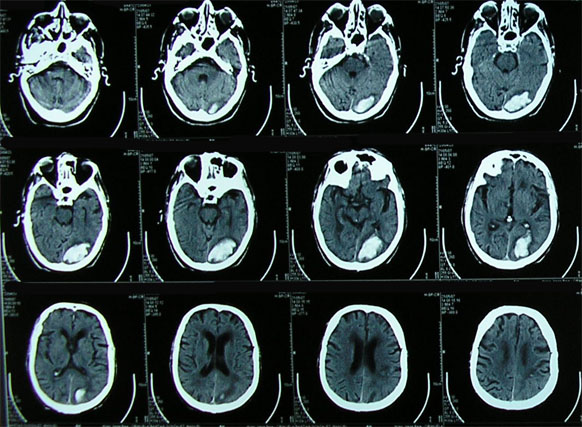

Son múltiples las ventajas de la TAC en estas regiones. Es bien conocida la utilidad de la TAC en sistema nervioso, fundamentalmente en la patología de guardia, en pacientes críticos y como rastreo de numerosas patologías. La TAC con cortes submilimétricos agrega un barrido mucho más detallado del parénquima encefálico y del cráneo, evitando los tan comunes artificios por “volumen parcial” y minimizando los artificios de Hounsfield. Con el agregado de las reconstrucciones multiplanares también mejora la performance del método en las patologías que afectan estructuras como el cuerpo calloso, la región pineal, el acueducto o el foramen magno (ej: lipoma del cuerpo calloso, estenosis del acueducto, quiste pineal, S de Chiari, etc.). La TAC agrega, además, el estudio del sistema vascular cerebral y cervical en conjunto, ya que la velocidad del tomógrafo permite el estudio de ambas regiones en tiempo arterial y venoso. De esta forma, nos ofrece la posibilidad de obtener mapas de perfusión del parénquima encefálico y una calidad superlativa en la evaluación de estructuras vasculares, arteriales y venosas mediante la angioTAC